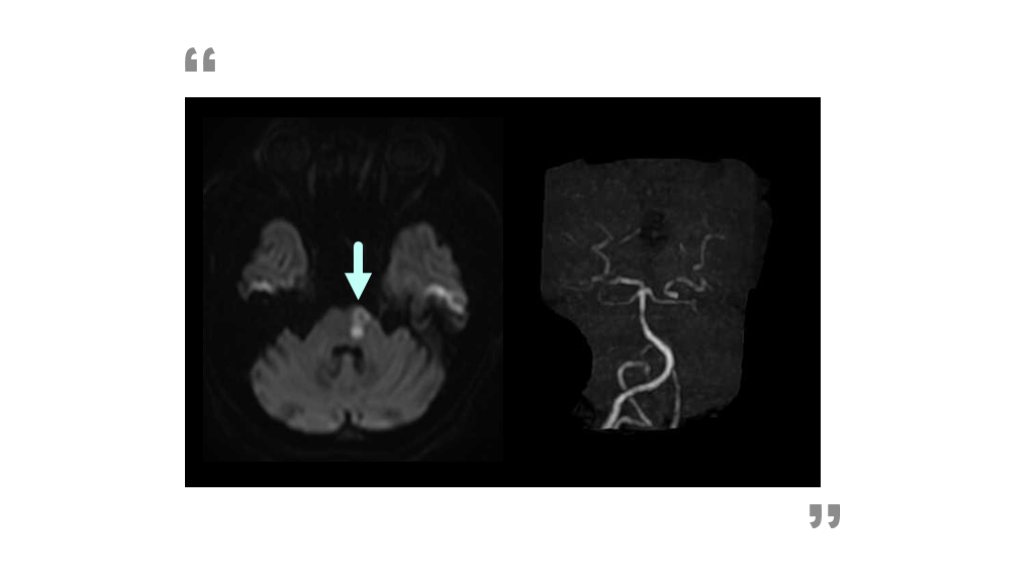

#50.

延髄外側梗塞 False negativeの例 DAY 1 ERでのMRI検査。     DWIで病変を指摘できない。     想定するのは左側延髄外側梗塞。

#51.

DAY2+DWI 3方向 DAY 2 翌日に撮像する + 2方向撮像することで、      2つのFalse negativeの克服。